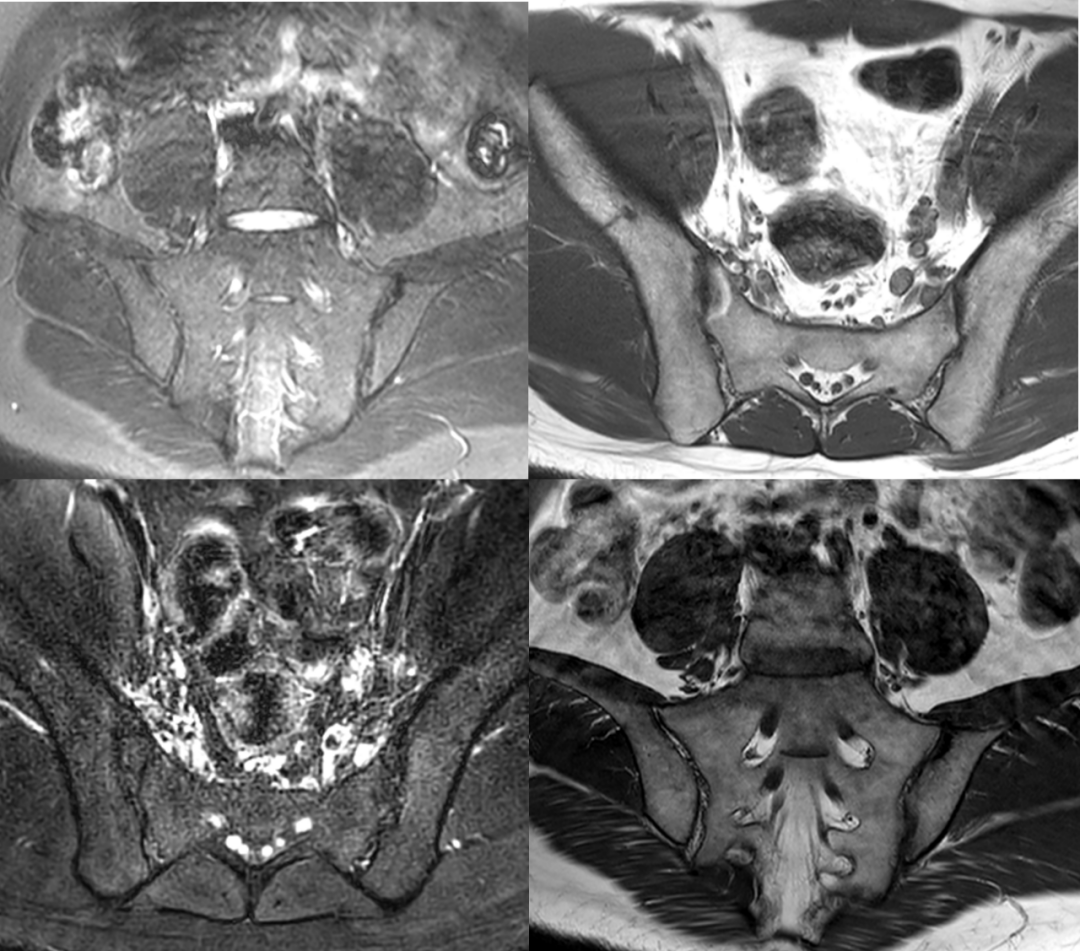

• 影像學(xué)檢查,如X光或核磁共振成像